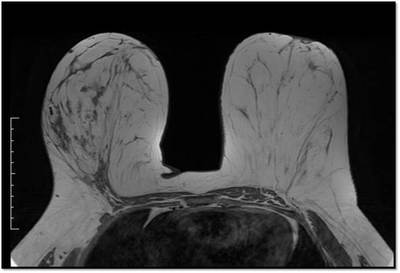

Breast MRI